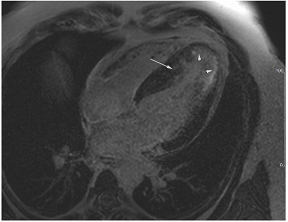

13. Hypertrophic Cardiomyopathy

In clinical practice, the differentiation of hypertrophic cardiomyopathy from hypertensive LVH is a frequent and difficult challenge, especially as the two pathologies frequently coexist. Hypertrophic cardiomyopathy is typically characterised by asymmetrical LVH, usually involving the septum, but any myocardial segment can be involved [54]. Hypertensive LVH often causes concentric LV remodelling, but asymmetrical LVH is not infrequent, and concentric hypertrophic cardiomyopathy is well-described particularly in non-sarcomeric phenocopies (Table 4D), so the pattern of remodelling alone may not be helpful unless it disproportionately affects, for instance, apical segments that do not hypertrophy in isolation in patients with HHD [55,56]. Patients with sarcomeric HCM also frequently develop a reverse septal curvature morphology with a loss of concavity of the septal endocardial surface (Table 4E,F) [57]. Other features that may point towards HCM as opposed to hypertensive heart disease include ancillary abnormalities such as elongation of the anterior leaflet of the mitral valve [58]; protrusion of the anterior leaflet into the LV cavity–26 mm or more (“night cap” mitral valve) [59]; the presence of numerous myocardial crypts [Table 4G] [59] (isolated myocardial crypts are likely within normal limits [60]); apical displacement of the papillary muscles; anteromedial displacement or duplication of the anterolateral papillary muscles; apico-septal muscle bundles (Table 4H) [61]; and accessory papillary muscles or anomalous direct insertion of papillary muscles onto the mitral valve [62]. Systolic anterior motion of the anterior leaflet of the mitral valve and the associated posteriorly directed MR and left ventricular outflow tract obstruction are more frequently seen in HCM than hypertensive heart disease but can occur in both settings, particularly if there is hypertension and isolated basal septal hypertrophy with hyperdynamic LV contractility in the elderly [63]. Some degree of LGE can be seen in approximately two-thirds of patients with HCM, most often in the areas of maximum hypertrophy [64]. The pattern and extent of enhancement are often very heterogeneous within as well as between patients [65]. Diffuse patchy mid-wall enhancement is frequently seen in advanced hypertensive heart disease with poor blood pressure control (Table 4I) but equally can be seen in HCM [47]. However, very dense organised fibrosis is more commonly seen in the latter, particularly in the so-called burned-out phase (Table 4J).

14. Fabry’s Disease